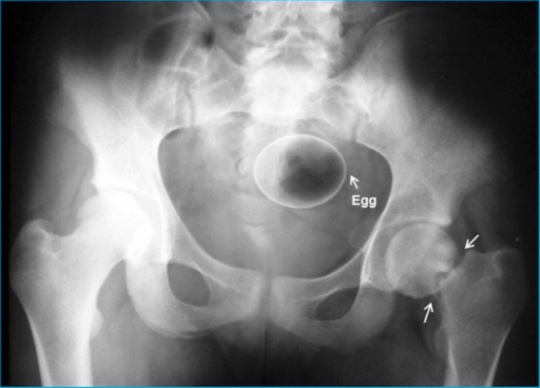

7. კვერცხი